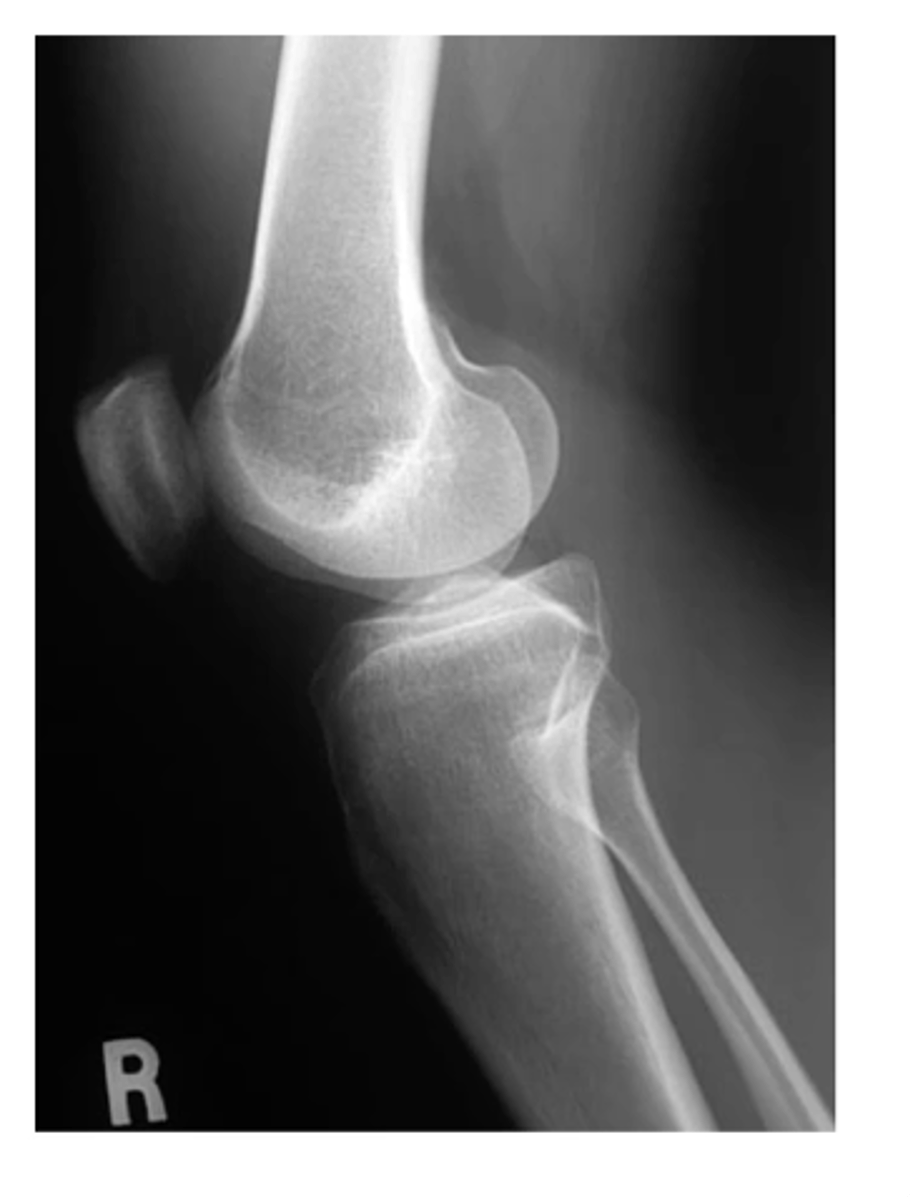

View: right lateral

Structure: right knee

Femur shifted MEDIALLY over tibia; patella shifted SUPRALATERALLY; bone spur on the lateral tibial plateau

Work through your "ABCS". Start with A: alignment.

Sclerosis along bilateral tibial plateaus -- more pronounced laterally (hallmark of OA, along with the bone spur noted in "A: alignment")

Work through your "ABCS". Start with B: bone density.

Loss of joint space along the lateral tibiofemoral component. Diminished joint space along the medial side.

Work through your "ABCS". Start with C: cartilage space.

Calcification superior to the patella, Baker's cyst on the posterior side, LOTS OF SWELLING

Work through your "ABCS". Start with S: soft tissue.